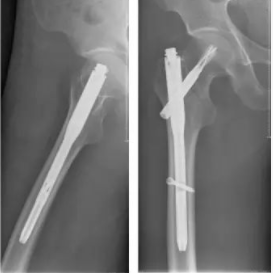

老年髋部骨折的新型术式——FNS治疗股骨颈骨折

老年髋部骨折的典型术式—Inter tan微创闭合复位内固定术